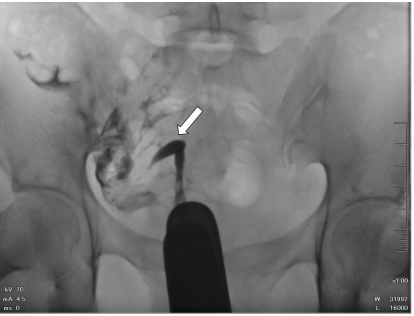

75.32歲女性,子宮輸卵管攝影檢查呈現如圖,箭號所指之敘述何者最正確? (A)子宮肌瘤 (B)單角子宮 (C)子宮內膜異位 (D)子宮(輸卵管)外孕